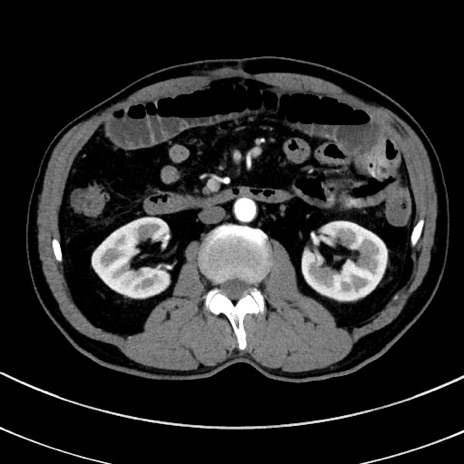

冠状断像

【症例】 60歳代男性

【主訴】 黒色吐物

【現病歴】 4日前から嘔気自覚、2日前の朝食後にも嘔気あり、自分で手で嘔吐反射起こし嘔吐したところ血が混ざっていたため受診。

【既往歴】 5年前汎発性腹膜炎を伴う急性虫垂炎で手術、高血圧、前立腺肥大症、高脂血症

【身体所見】 腹部正中に手術癩痕あり 腹部平坦・軟圧痛なし膨満感あり

【データ】WBC 8400、CRP 4.54